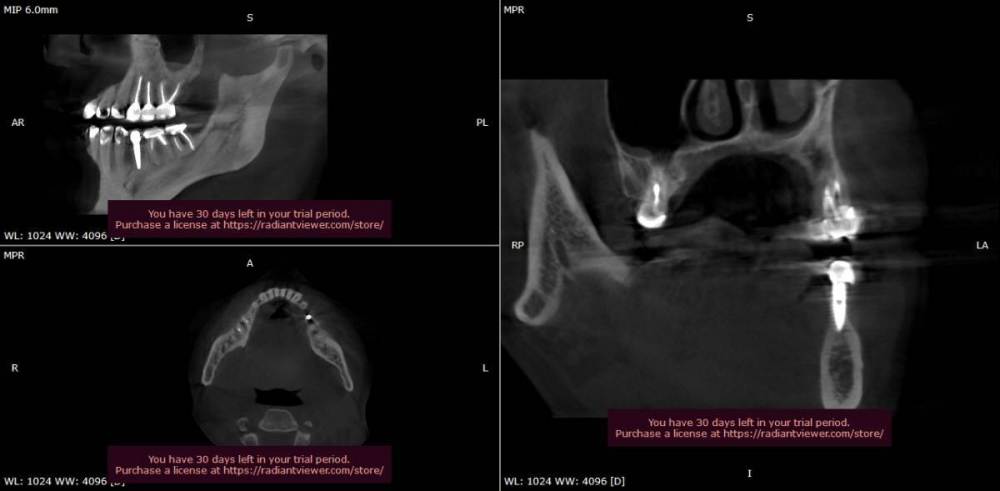

Ljocha Опубликовано 31 августа, 2022 Автор Поделиться Опубликовано 31 августа, 2022 приветствую! хотел бы спросить различные мнения: как считаете, такое иметь право на жизнь или надо выкручивать? установлен в апреле 2020, в приложении 2-х летняя динамика спасибо! Ссылка на комментарий